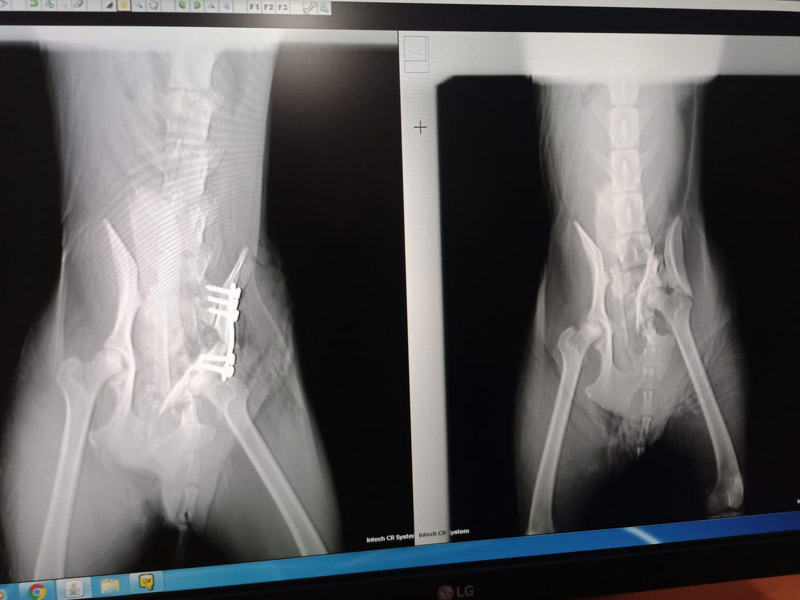

Der kleine Saul wurde inzwischen operiert und wir haben unseren spanischen Tierschützern unsere Hilfe zugesagt.